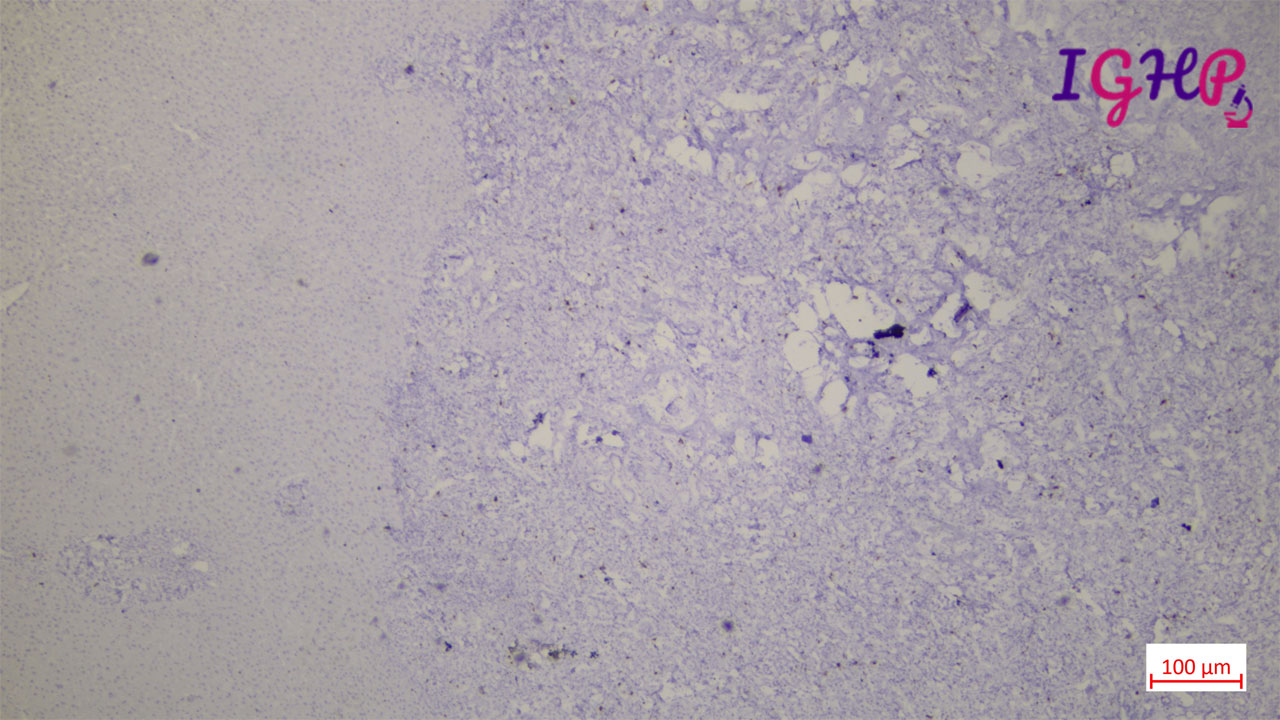

Ki67 IHC showed similar expression as surrounding ductulesin portal tracts